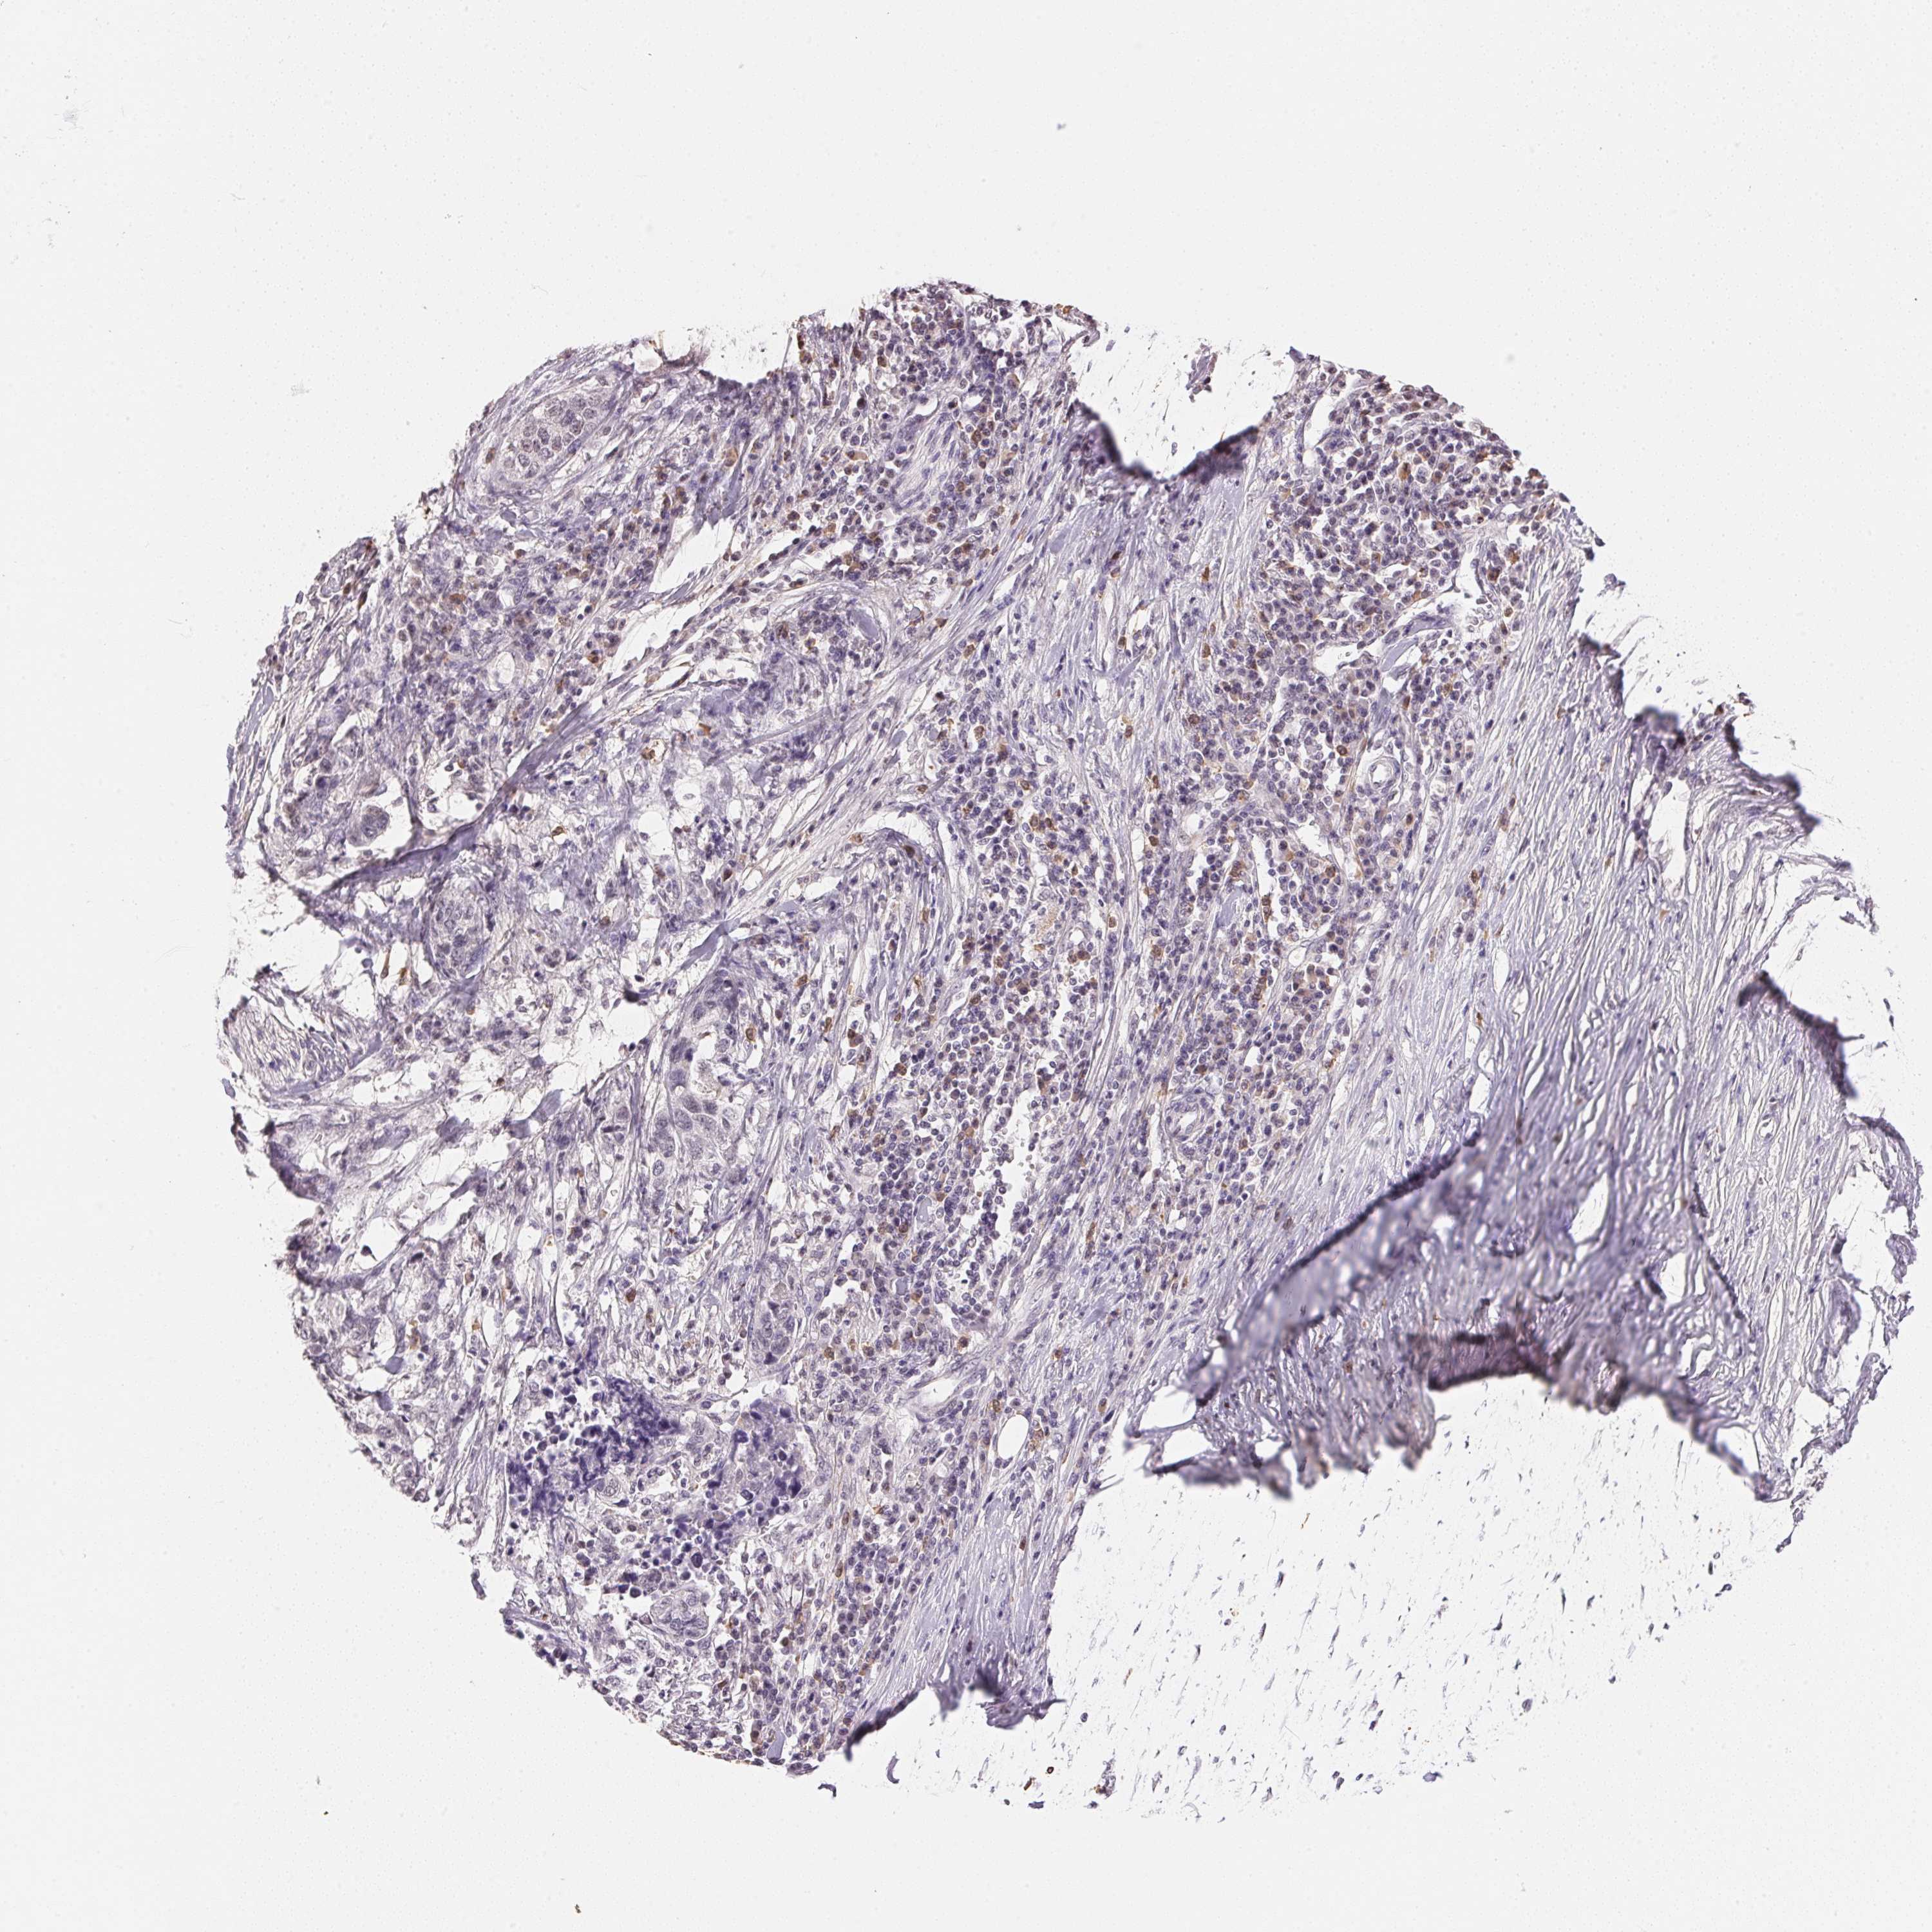

STOMACH CANCER - Protein expressioni

A mouse-over function shows sample information and annotation data. Click on an image to view it in a full screen mode. Samples can be filtered based on level of antibody staining by selecting one or several of the following categories: high, medium, low and not detected. The assay and annotation is described here.

Note that samples used for immunohistochemistry by the Human Protein Atlas do not correspond to samples in the TCGA dataset.

Antibody stainingi

Antibody staining in the annotated cell types in the current human tissue is reported as not detected, low, medium, or high, based on conventional immunohistochemistry profiling in selected tissues. This score is based on the combination of the staining intensity and fraction of stained cells.

Each image is clickable and will lead to virtual microscopy that enables deeper exploration of all samples and also displays staining intensity scores, fraction scores and subcellular localization as well as patient and tissue information for each sample.

Antibody HPA051804

Antibody HPA063581

Staining

High

Medium

Low

Not detected

Intensity

Strong

Moderate

Weak

Negative

Quantity

>75%

75%-25%

<25%

None

Location

Nuclear

Cytoplasmic/membranous

Cytoplasmic/membranous,nuclear

Adenocarcinoma, NOS